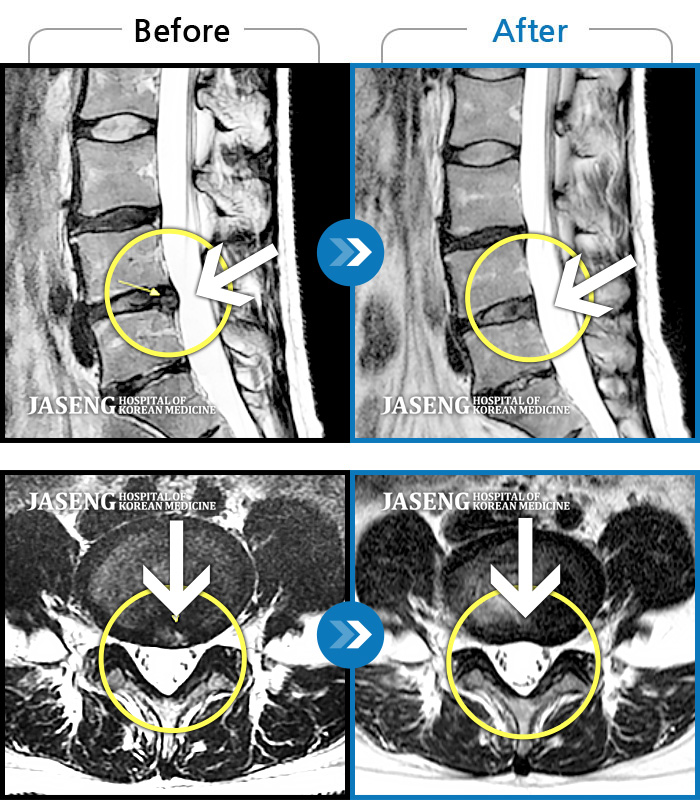

Before

After

허리 통증과 함께 발끝 저림이 1년 이상 되었으며 최근 1-2개월 사이에 증상이 급격히 심해져 우측 다리 앞 뒤가 당기고 힘이 빠져 본원에 내원함

2023.11.20 ~ 2024.08.12